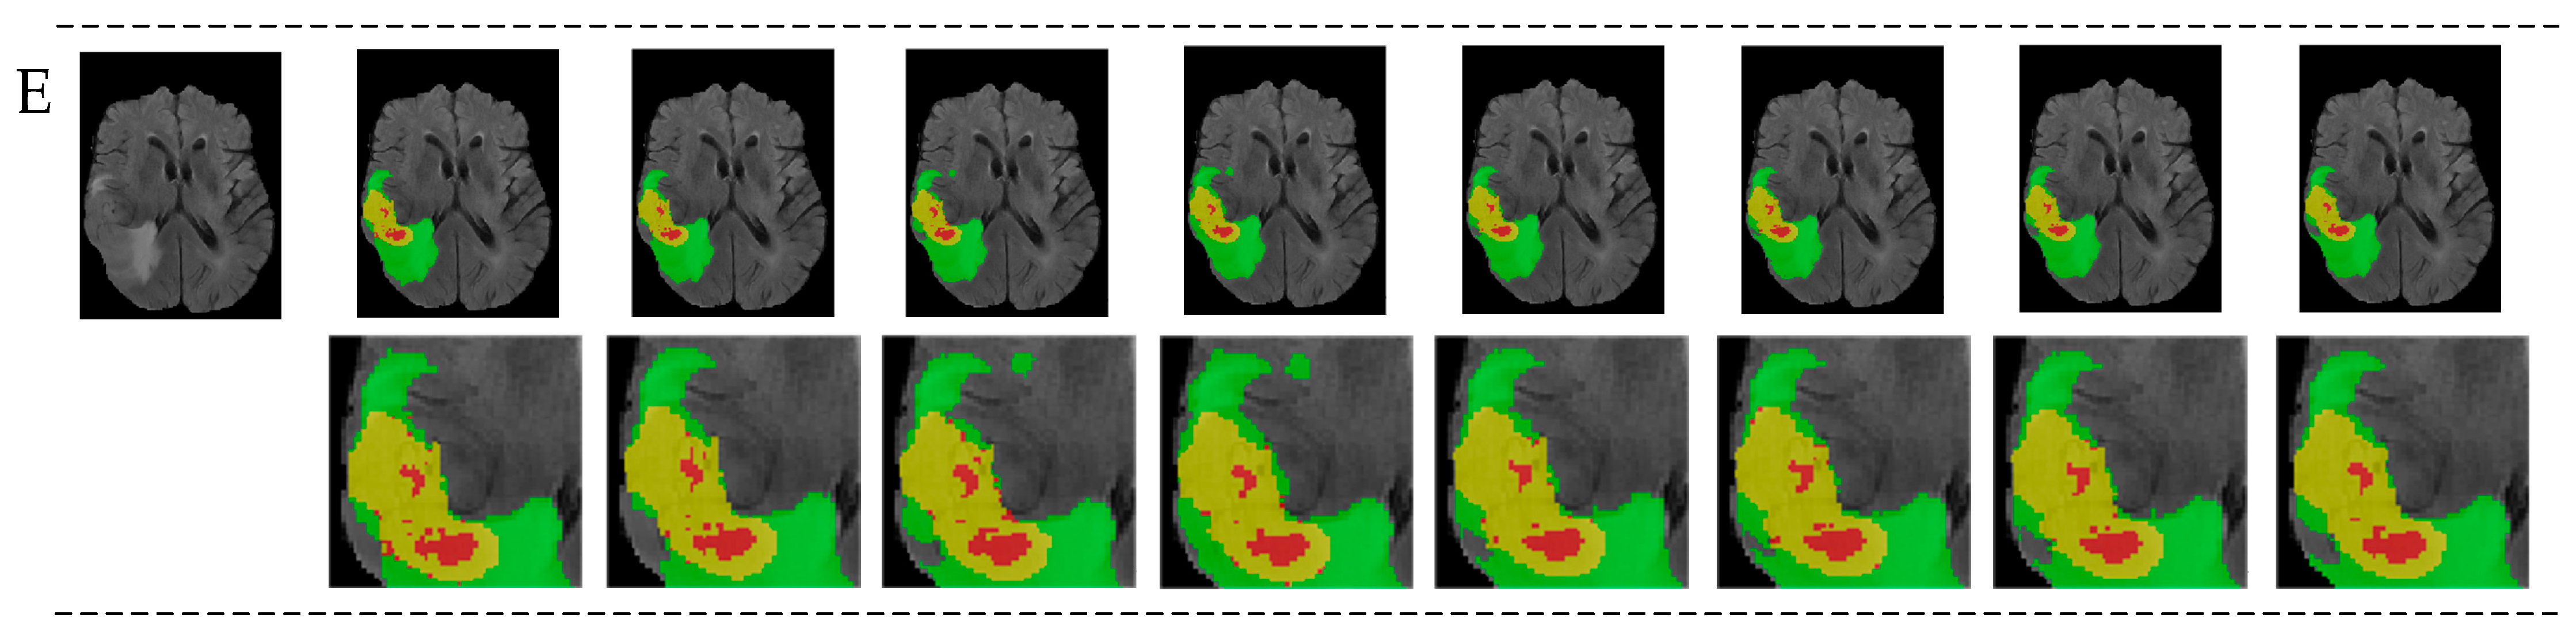

The results show that our network slightly improved in terms of TC and ET; that is, our network performs better than the baseline in small target segmentation. Compared to other networks, ours may not be the best on a single indicator, but our average results and ET values are the highest. Regarding the BraTS dataset, the final segmentation results are divided into three parts: whole tumor (WT), tumor core (TC), and enhancing tumor (ET). They have an inclusive relationship, meaning that WT encompasses both TC and ET, with ET being included within TC. If there is an emphasis on enhancing the focus on local detail features, the ET results are likely to improve. This indicates that our segmentation performance for small targets is the best among the compared networks, mainly due to the incorporation of local detail features. Figure 8 shows the visualization results of the GETNet model on the BraTS2021 dataset, in which five cases were randomly chosen. The medical cases, as shown in sequences A, B, C, D, and E of Figure 8, were segmented by GETNet. The figures from left to right are, respectively, FLAIR, 3DUNet, Att-Unet, UNetr, TransBTS, VT-UNet, SwinUNet3D, the results segmented by GETNet, and the ground truth. Green, yellow, and red represent WT, TC, and ET, respectively. In general, the results of GETNet are close to the labeled ground truth. Compared to the network with only convolutions, the results of our model are the best. Our network also performs better than the networks based on a Transformer. Overall, our architecture and modules achieved better results in relation to BraTS2021, providing a good basis for subsequent research.

Figure 8. Visualization results for medical cases. From left to right: FLAIR, 3DUNet, Att-Unet, UNETR, TransBTS, VT-UNet, SwinUNet3D, the results segmented by GETNet, and the ground truth. (AE) are five cases were randomly chosen on the BraTS2021 dataset. Green, yellow, and red represent WT, TC, and ET, respectively.